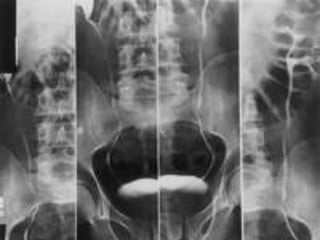

URETERS

- peristalsis.

- Stasis of contrast.

- Medial deviation.

- Lateral deviation.

- Anatomic narrowing.

- Ureter diameter (8mm).

- Filling defect.

 Medial deviation of the ureter should be considered

when the ureter overlies the ipsilateral lumbar

pedicle.

 lateral deviation should be considered when the

ureter lies more than 1.5 cm beyond the tip of the

transverse process.